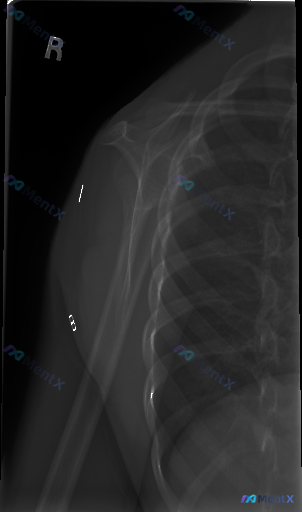

- 体位:右侧肩关节Y位(肩胛骨侧位)

- 影像所见:肱骨头与肩胛盂中心对位良好,无明显前后脱位;骨皮质连续,未见明显骨折线、塌陷或成角;关节间隙尚可;肩峰下及周围软组织无明显肿胀或异常高密度;也未见明显骨赘或严重骨质增生/疏松。

初步看下来,这张X光未见明确的器质性骨异常。